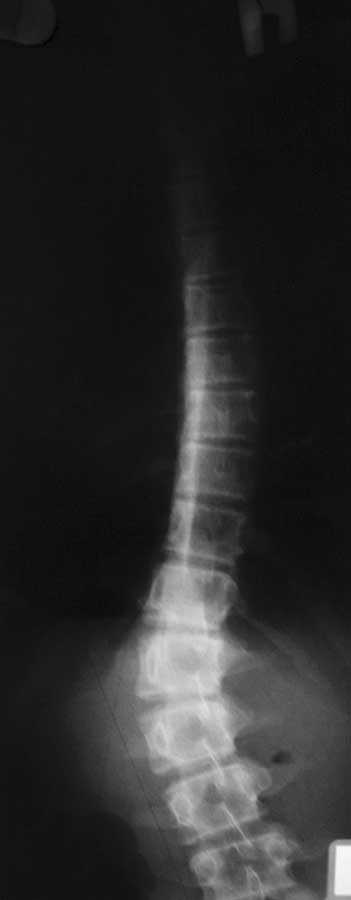

Re: Сколиоз у девочки 13 лет

послал Григорий 24 Февраль 2013, 15:10

Вот рентгенограммы.